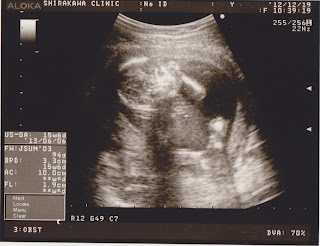

Through asking around and the internet, I was really fortunate to find a clinic that has a few English speaking doctors and nurses and is only about a 20 minute bike/10 minute car ride from our house. A wonderful Japanese friend of ours made an appointment for me when I was about 10 weeks along, which is when they advise you to come in to confirm your pregnancy. She also came with me to the first two appointments to help fill out all of the initial paperwork and make sure I knew what was generally expected of me during appointments. I was a bit surprised that they used ultrasound to confirm pregnancy instead of simply doing a blood test as they would in Canada. There are a lot of differences in the use of ultrasound during pregnancy in Japan vs. Canada and I think I will go into further detail about this in a future post.